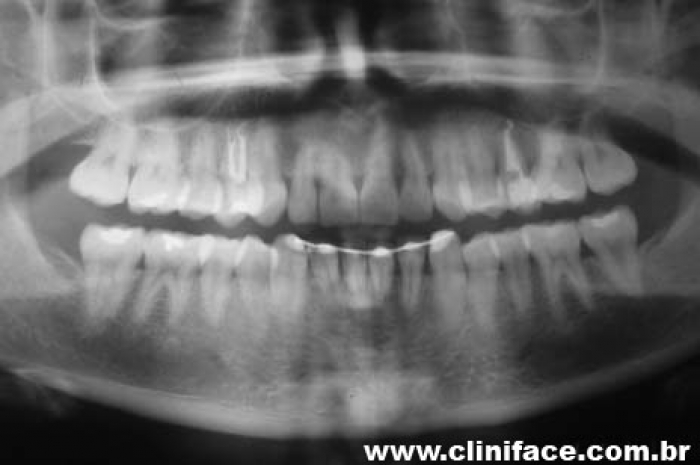

Rx final